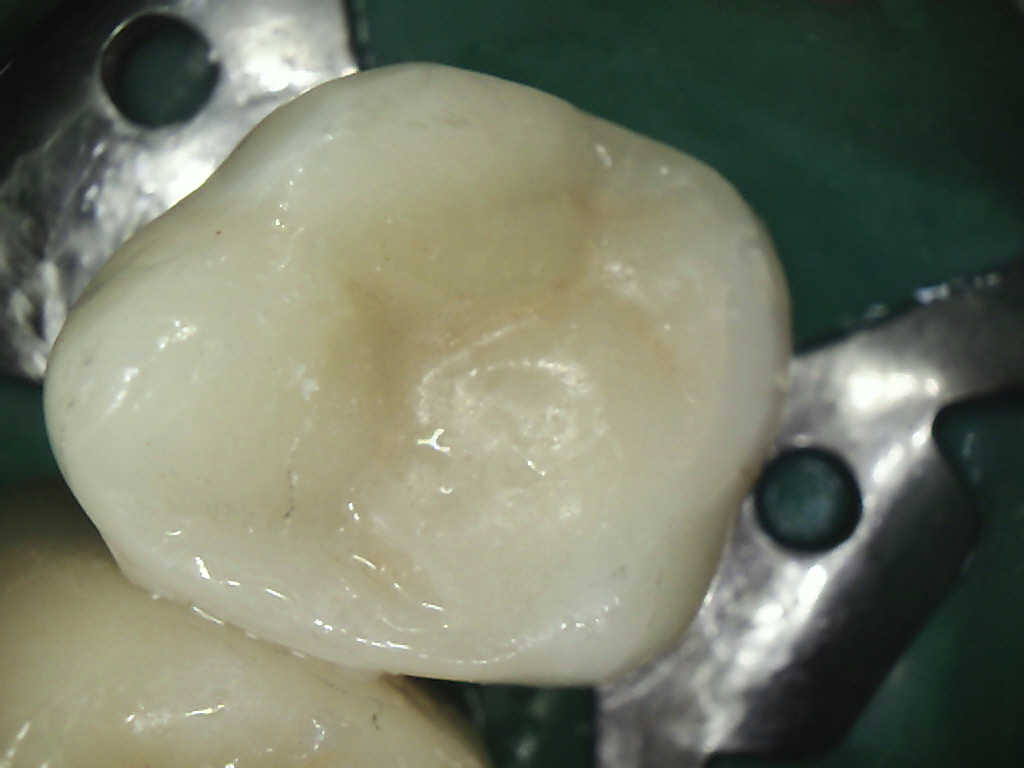

Kleine Defekte der Zahnhartsubstanz werden mittels einer einfachen Kompositfüllung therapiert (zahnfarbener keramikverstärkter Kunststoff, der im Mund des Patienten

mit Kaltlicht ausgehärtet wird) .